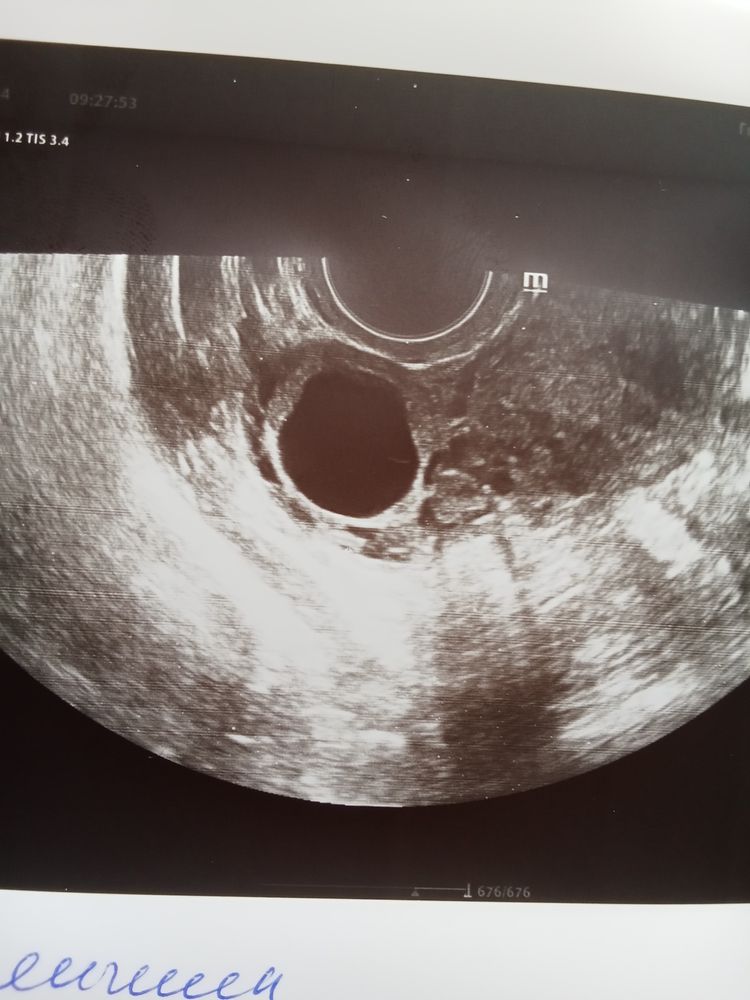

Фолликулометрия, финальная версия 😁

У меня тоже в прошлом цикле бхб ,а в этом пришла на фолликулометрию отследить а мне сказали что овуляция была и образовалась киста жт, но не сказали что это может быть связано с бер.)а как это кистозное жт с кровотоком?

Дана Ковалева, киста жт это кистозное образование жт, а кровоток показатель работы жт. По простому отличное жт. Жду от вас //, какой дпо?